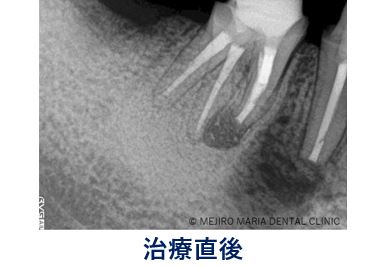

手術を開始したところ、右下5番根尖頬側に見逃し根管(手のつけられていない根管)を確認し、通法通り、根尖側3mmを切断し、逆根管形成後MTAにて逆根管充填を行った。

また、手術直後のレントゲン写真から比較すると、術後3ヶ月のレントゲン写真では順調に骨が作られていることが確認できる。